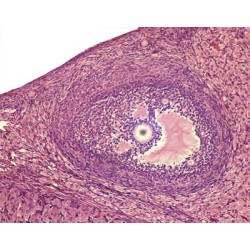

Histologia